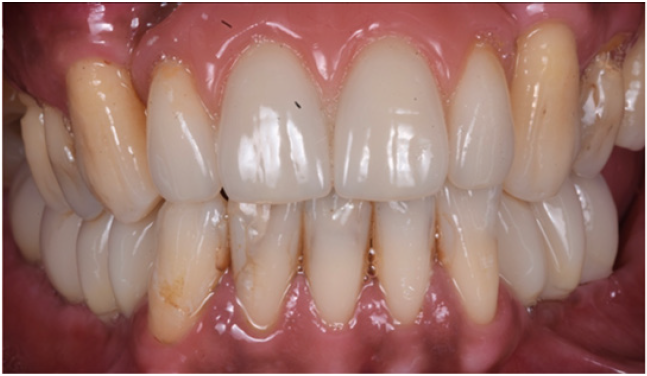

Figure 23: Clinical view of the long term acrylic restoration.